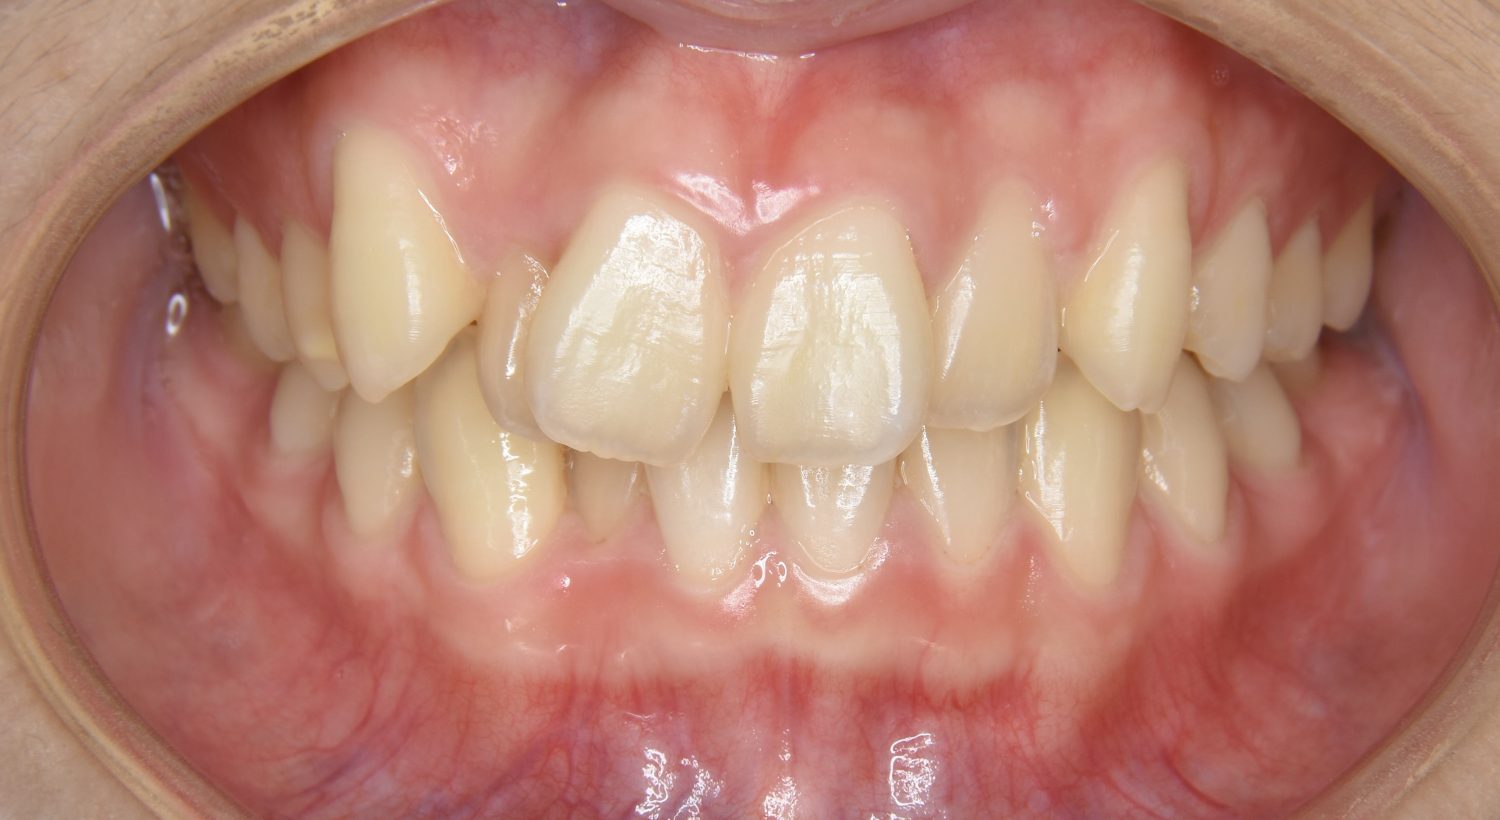

叢生の症例紹介①

Before

After

主訴

前歯のガタガタが気になる。

治療内容

上顎左側第一小臼歯を抜歯し、アライナー(インビザライン)にて治療を行いました。

左上の側切歯が完全に内側に入り込んでいる状態でした。左上の第一小臼歯のみ抜歯を行い治療を行うことで機能面および審美面を改善しました。